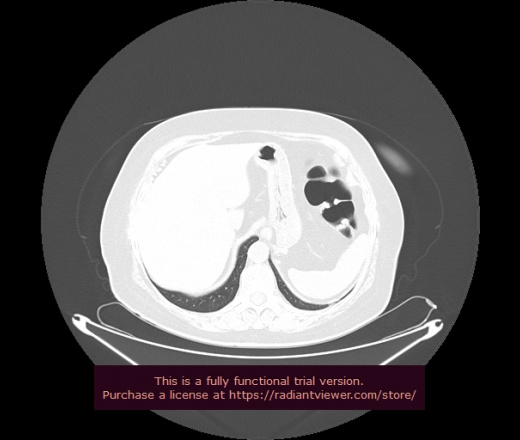

Уважаемые коллеги, если имеется интерес, сможете ли Вы спрогнозировать дальнейшее +-одинаковое течение процесса у 4 данных разных пациентов? Зацепиться где-то можно очень просто, где-то нельзя.